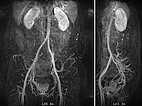

In dynamic contrast-enhanced MR angiography (late phase over 2 min after contrast administration, left coronal and right sagittal), the lesion shows no contrast enhancement or increased vascularization. It is practically invisible.